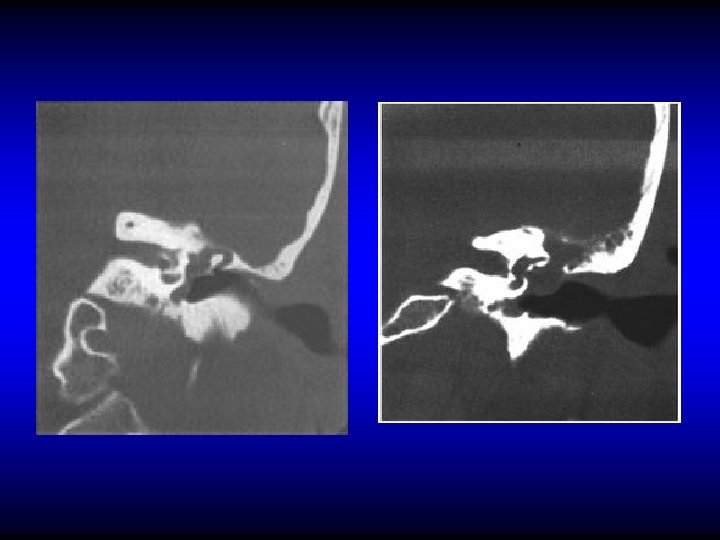

Investigations • Audiometry • Bacteriology • CT (mainly in the AA type)

DIAGNOSIS OF ACUTE MASTOIDITIS & MASTOID ABSCESS • General constitutional manifestations • Tympanic membrane changes • Otorrhea and reservoir sign • Retroauricular tender ness and red ness • Subperiosteal and Bezold’s abscess • Imaging

NORMAL ACUTE MASTOIDITIS

MASTOID ABSCESS